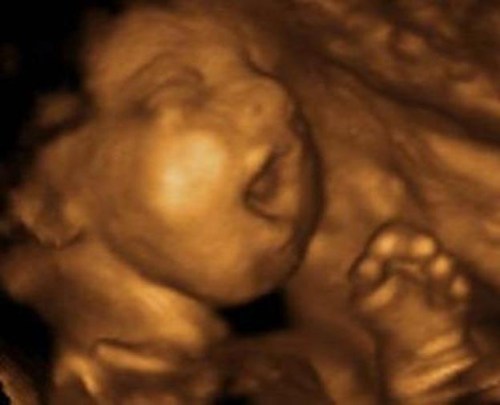

MARYLAND: The Maryland Senate is considering the “Pregnant Person’s Freedom Act of 2022” that would prohibit investigations and criminal prosecutions for women and medical professionals for a “failure to act” in relation to a “perinatal death.” Since a 2020 law defines “perinatal care” as the “provision of care during pregnancy, labor, delivery, and postpartum and neonatal periods,” this bill could mean that during the first four weeks of their lives, human babies would have no legal protection from abuse or neglect … something Maryland law guarantees to newborn baby animals.